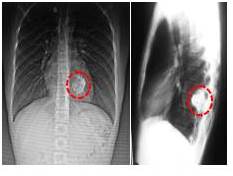

Radiografía simple de tórax póstero anterior y lateral, con imagen radiopaca de apariencia redondeada, de unos 5 cm de diámetro aproximadamente, localizada a nivel del décimo (10o) arco costal posterior izquierdo (Figura 1).